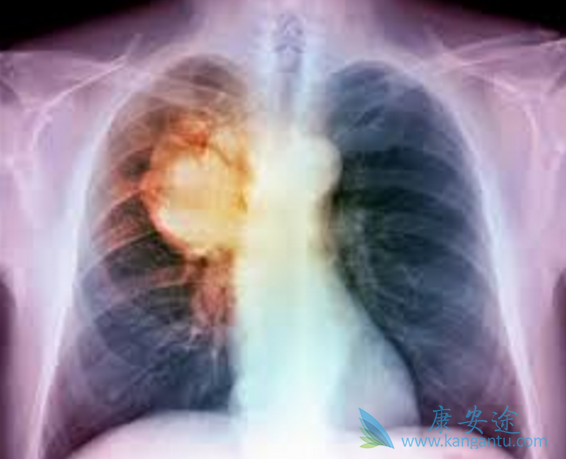

生存获益是晚期肺癌治疗最重要的考量因素。截至最近一次LUX-Lung 7研究总生存(OS)分析点(2016年12月5日),阿法替尼(GILOTRIF)和吉非替尼的中位OS分别为27.9和24.5个月(HR 0.85 (0.66–1.09),P=0.195),标志性的24、30、48个月OS率分别为61% vs 51%、48% vs 40%和28% vs 20%。在接受后续第三代EGFR TKI治疗的患者中,与吉非替尼相比,阿法替尼有改善OS的趋势(NE vs 48.3个月; HR 0.49 (0.20–1.19))。

一线阿法替尼(GILOTRIF)治疗患者接受后续第三代EGFR TKI治疗的生存率令人惊叹,3年OS率可达到93%!如果靶向治疗耐药不可避免,则初治药物的选择就非常关键。LUX-Lung 7更新数据表明,除了能够显著减少疾病进展风险外,一线选择阿法替尼可为患者带来持续的生存获益,且安全性和疗效优势在亚组中保持一致。

LUX-Lung3/6/7事后分析从长期生存者的角度证实了上述结论。对这三个研究中阿法替尼(GILOTRIF)长期治疗反应者(LTR,定义为阿法替尼治疗≥3年)的分析显示,有10%~12%的阿法替尼治疗患者能达到长期治疗有效。与总体试验人群相比,其中女性和Del19突变阳性患者比例更高;阿法替尼中位治疗持续时间分别为50个月/56个月/42个月,长期治疗与剂量调整和基线时的脑转移无关。而在LUX-Lung7中,仅4%的吉非替尼治疗患者为LTR。